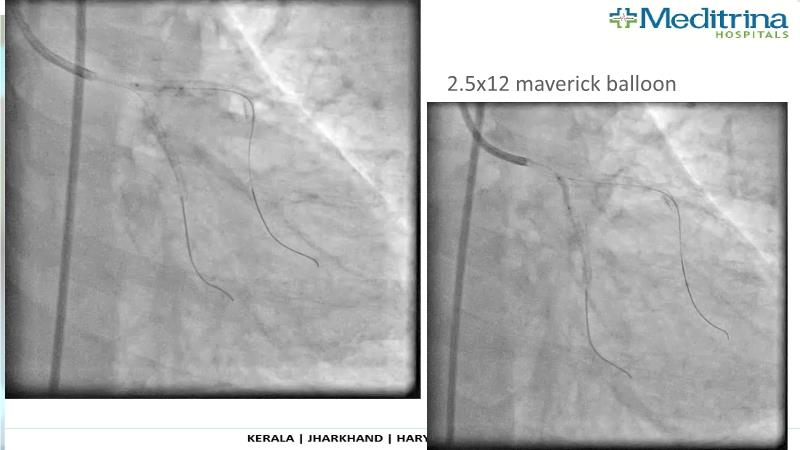

- To define the use of OCT in PCI of complex coronary lesions